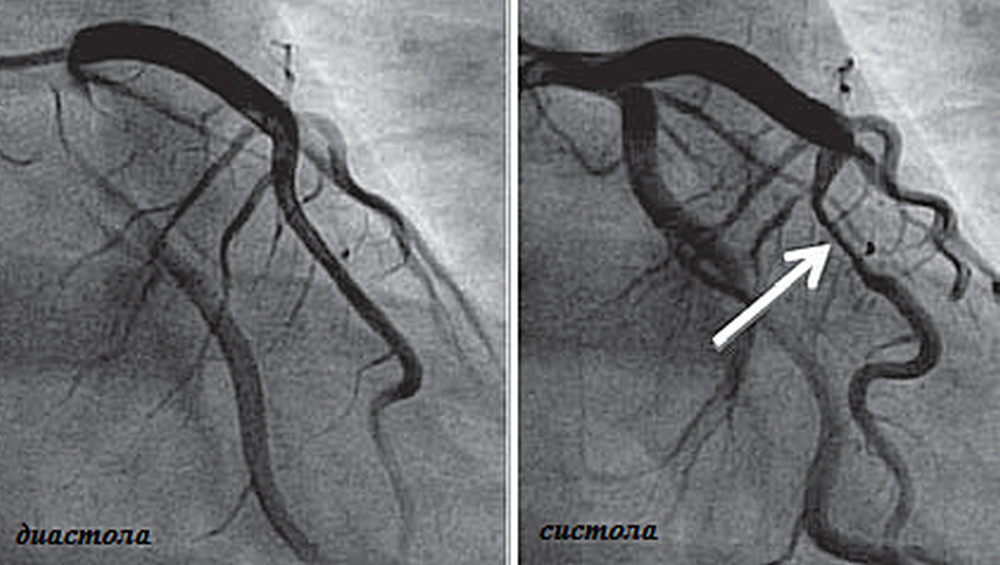

Хроническая окклюзия артерий: причины, симптомы и лечение